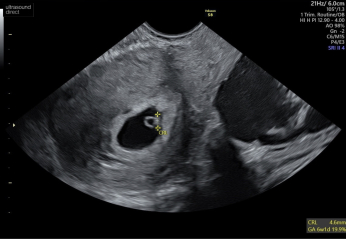

I’ll be honest I was a complete nervous wreck today. I had a internal scan and I couldn’t stop shaking even after we saw the heartbeat but now I feel

so much better X

Keeping everything crossed for baby number three

Cramping and spotting 5 weeks

@TTCournumberthree that’s amazing news I’m so pleased for you! Lovely scan pictures too !!

Oh @TTCournumberthree im so pleased for you!! I had my scan too and saw the little heartbeat fluttering away. I’m 6w so we are so close! X

@bubble55 little june babies! I really went in expecting the worst. It’s such a relief isn’t it x

@bubble55 yes definitely would have shifted any old blood. We were just dumbfounded that it was all ok, so excited though x